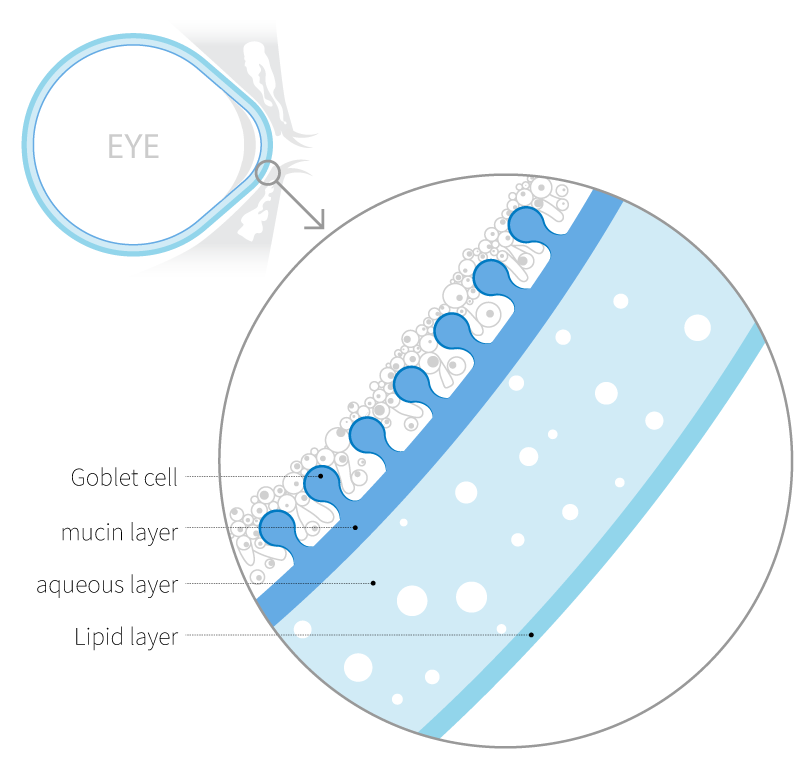

The Tear Film

Dry eye disease occurs due to abnormalities in the tear film and is often accompanied by ocular discomfort and keratoconjunctivitis.The tear film consists of the mucin, aqueous, and lipid layers, and accurate diagnosis of the affected layer is essential for appropriate treatment of dry eye disease.Although methods exist to evaluate each layer of the tear film, there is still a lack of adequate techniques to specifically assess the mucin layer.

Goblet cells, located in the conjunctival epithelium, secrete the mucin MUC5AC to form the mucin layer of the tear film. They play a key role in maintaining tear film stability and lubricating the ocular surface. When goblet cells are damaged or reduced in number due to inflammation or external stimuli, mucin secretion declines, leading to tear film instability and the onset of ocular surface diseases such as dry eye.